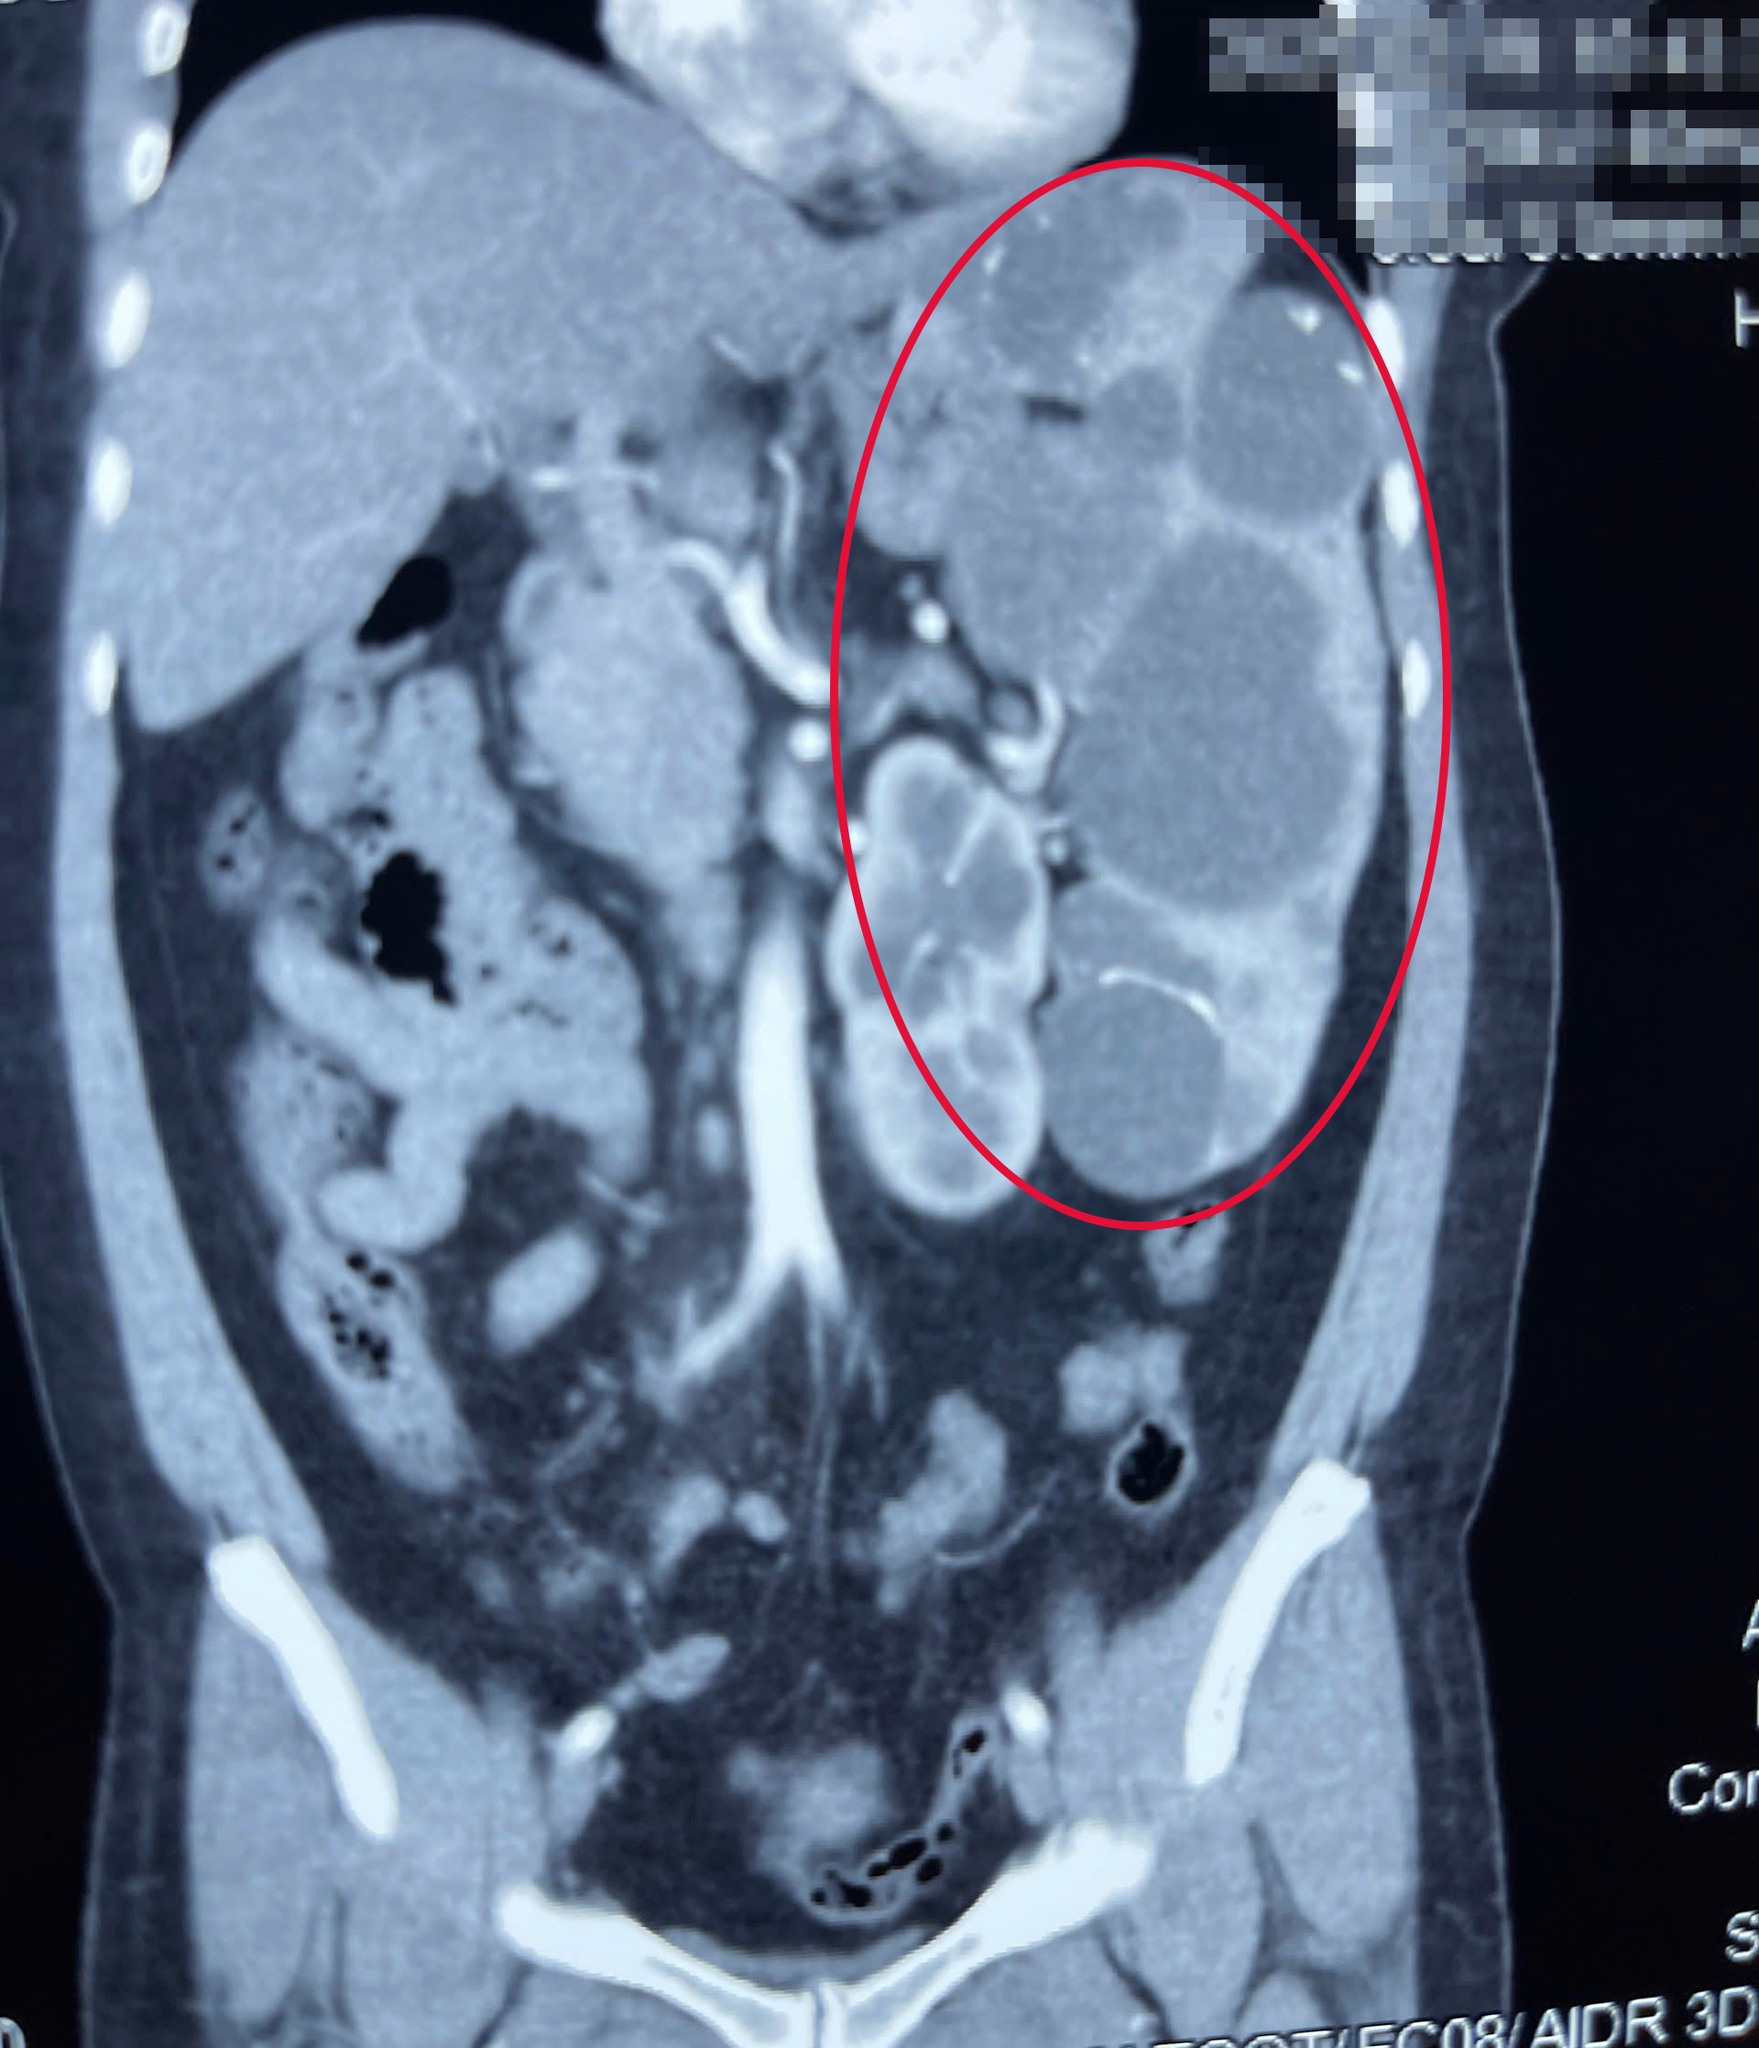

Los resultados de la tomografía computarizada abdominal muestran un agrandamiento anormal del bazo. Foto: BVCC

En la Clínica de Cirugía General, se le solicitó al paciente una tomografía computarizada abdominal. Los resultados mostraron un bazo anormalmente agrandado, que ocupaba la mayor parte del abdomen izquierdo, acompañado de numerosos quistes de gran tamaño.

Tras consultar y evaluar el estado del paciente, los médicos decidieron realizar una cirugía para extirpar todo el bazo y extraer el quiste. Dado que el bazo del paciente era demasiado grande, el médico optó por una cirugía abierta con una incisión de unos 15 cm, extirpando todo el bazo, que pesaba 1300 gramos, 40 veces más que un bazo normal (que pesa tan solo unos 32 gramos).